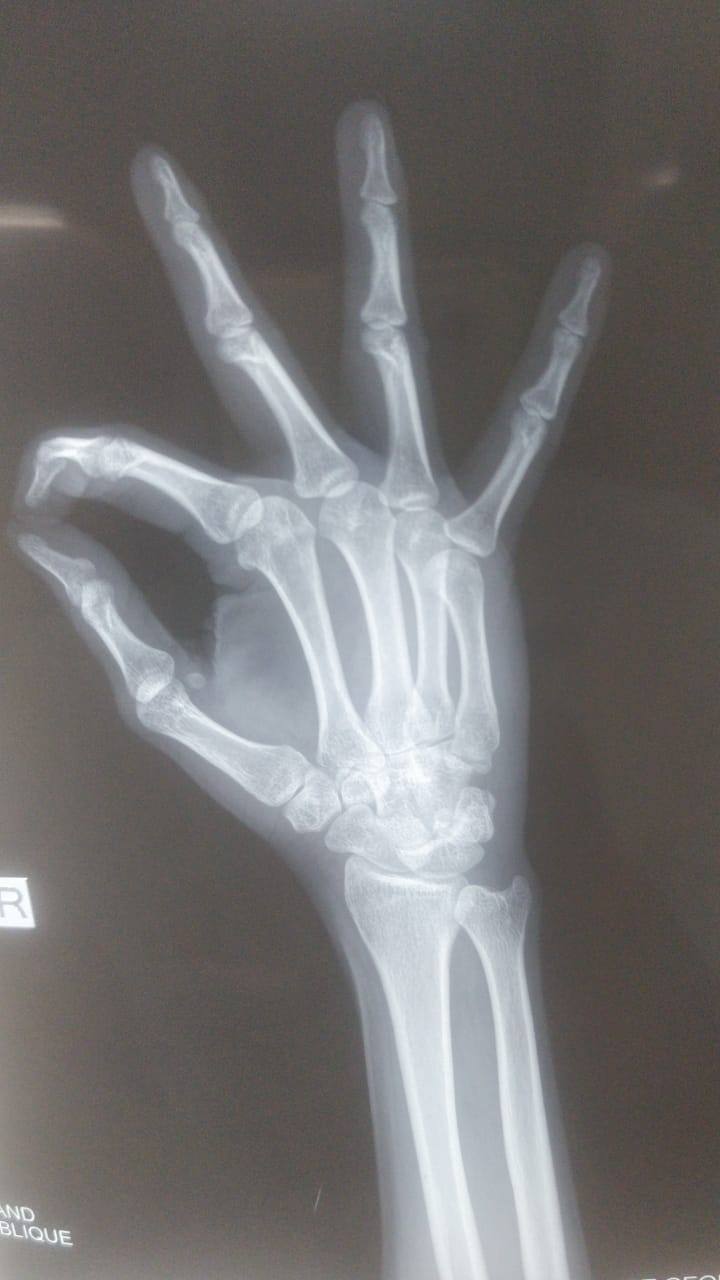

5th metacarpal hair line fracture Required surgery or not? Because doctor suggest me for surgery please reply as soon as possible sir.

5th metacarpal hair line fracture Required surgery or not ??